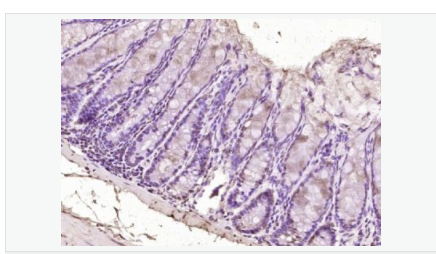

交叉反應:Human,Mouse(predicted:Rat,Dog,Pig,Cow,Rabbit) 推薦應用:IHC-P,IHC-F,ICC,IF,ELISA

產品應用ELISA=1:5000-10000 IHC-P=1:100-500 IHC-F=1:100-500 ICC=1:100-500 IF=1:100-500 (石蠟切片需做抗原修復)

免 疫 原KLH conjugated synthetic peptide derived from human SOX7:42-100/388

Widely expressed in adult and fetal tissues. Present both in mesenchymal and epithelial cells in some adult tissues, including colon. Tends to be down-regulated in prostate adenocarcinomas and colorectal tumors due to promoter hypermethylation.